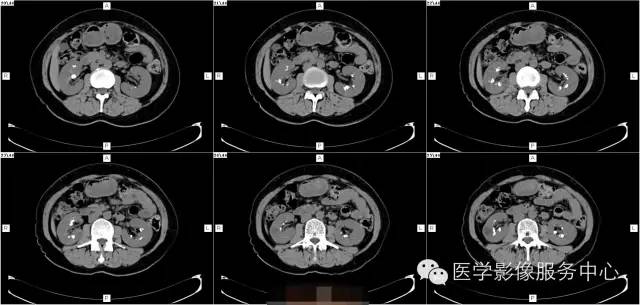

病史:

女,37岁,血尿一周

髓质海绵肾(简称MSK)又称Cacchi Ricci disease,是一种先天发育性肾髓质囊性病变,发生率约1:2000-5000,多见于40-60岁男年,70%为双侧肾脏发病,病变局限于髓质范围内,常累及两侧肾的多数锥体和乳头,形成许多数毫米的囊腔使髓质如海绵状,故名海绵肾,病理特点为集合管远端扩张,形成圆形或不规则型囊腔,囊内壁衬以立方或扁平上皮,囊内充溢脱离的上皮及钙化形成的小结石。

3、CT平扫表现一个或多个肾锥体内散在或蔟团状多发结石,呈花瓣样或扇形分布;部分腹部平片阴性,CT平扫可发现肾锥体内细小的结石。增强扫描表现扩张的肾集合管内有条纹状、刷状、小囊状或扇形的造影剂浓聚。部分患者肾实质内可见多发小囊肿。

1、肾钙盐沉积 :为肾集合管内及其周围弥漫性钙盐沉积,病变广泛,但不伴有集合管扩张,常见于肾小管酸中毒、甲旁亢、特发性高尿酸钙等

2、肾结核 病变不局限于肾乳头部,累及范围广,病灶不规则, IVP检查可显示肾盏虫噬样改变。

3、肾盏内散在小结石与不典型髓质海绵肾鉴别 海绵肾小结石位于肾乳头内,很少大于5mm,位置固定 ,IVP检查可见集合管囊状扩张,B超、CT检查可进一步明确诊断。

4、肾乳头坏死形成的钙化 病变位于肾盏顶部或锥体的尖端,钙化呈环状或三角形,密度均匀,病变中心因乳头坏死呈空腔改变,可伴肾盏变形和肾功能损害。